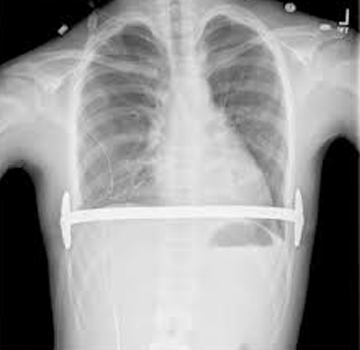

VAKUM TEDAVİSİ - Ameliyatsız Yöntem

VAKUM TEDAVİSİ

Ameliyatsız Yöntem

Pektus ekskavatumun tedavisinde seçilmiş bir grup hastada uygulanan vakum (vacuum bell) tedavisi ...